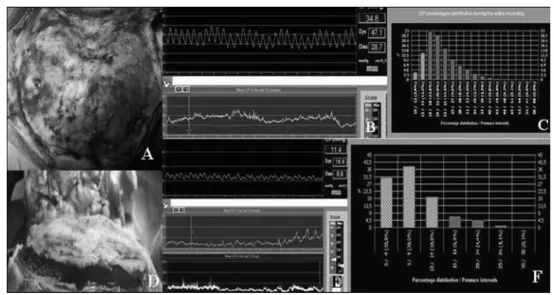

图3枕部游离扩大术

a.术中照片(同图1患儿)示枕骨在颅颈交界水平明显后缩,与术前CT一致

b.枕部扩大前持续ICP监测典型曲线:可见病理性高压及异常波

c.枕部扩大前48小时ICP监测柱状图:90%时间ICP>12 mmHg(红色柱)

d.游离枕骨片完全离断后:因颅内压增高,骨片自动浮起于硬膜表面

e、f.枕部扩大术后ICP监测:单曲线及48小时柱状图均显示ICP恢复正常